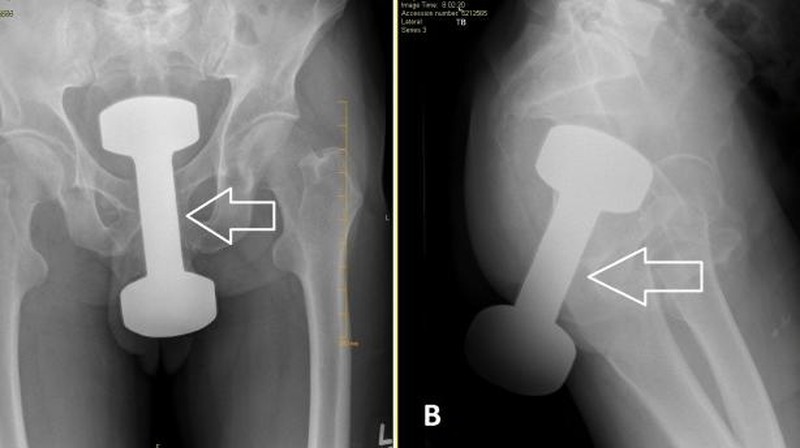

Pria 50 tahun datang ke IGD dengan dumbell 5 pon (2,2 kg) tersangkut di rektum. Setelah prosedur sedasi dan manuver khusus, barbel berhasil dikeluarkan dan pasien pulang dengan kondisi baik. (Foto: Cureus Journal)